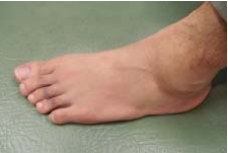

35 如下圖,急性外踝扭傷,下列何種功能活動受限最大? (A)內翻(Inversion) (B)外翻(Eversion) (C)背屈(Dorsiflexion) (D)蹠屈(Plantaflexion)